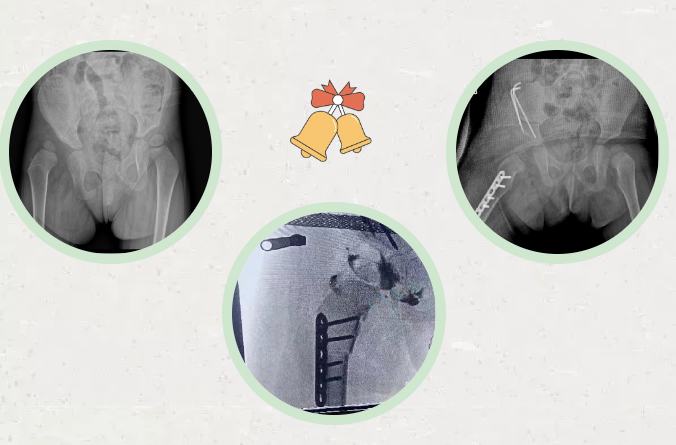

拍摄X光片后

贝贝存在发育性髋关节脱位

(DDH)

1月26日

由徐刚教授主刀

为贝贝完成

Salter骨盆截骨术

采取的是以前缘缺损为主的

髋关节发育不良的经典手术方案

术中切断部分内收肌

“T”形切开关节囊

复位脱位的髋关节

股骨近端去旋转短缩截骨

Salter骨盆截骨

术后进行髋关节人字石膏固定

手术非常成功